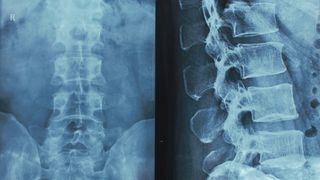

12/20/2024 5:22:15 PM Can Medical Malpractice Cause a Spinal Cord Injury? By Joshua H. Meyeroff Ryan T. Keating Spinal cord injuries are among the most serious medical conditions, often leading to life-altering physical, emotional, and financial...

12/29/2025 3:53:37 PM When a Missed Diagnosis Changes Everything: Delayed Treatment of Spinal Epidural Abscess By Joshua H. Meyeroff Ryan T. Keating A spinal epidural abscess rarely announces itself as a medical emergency. For many patients, it begins quietly with back pain that feels...